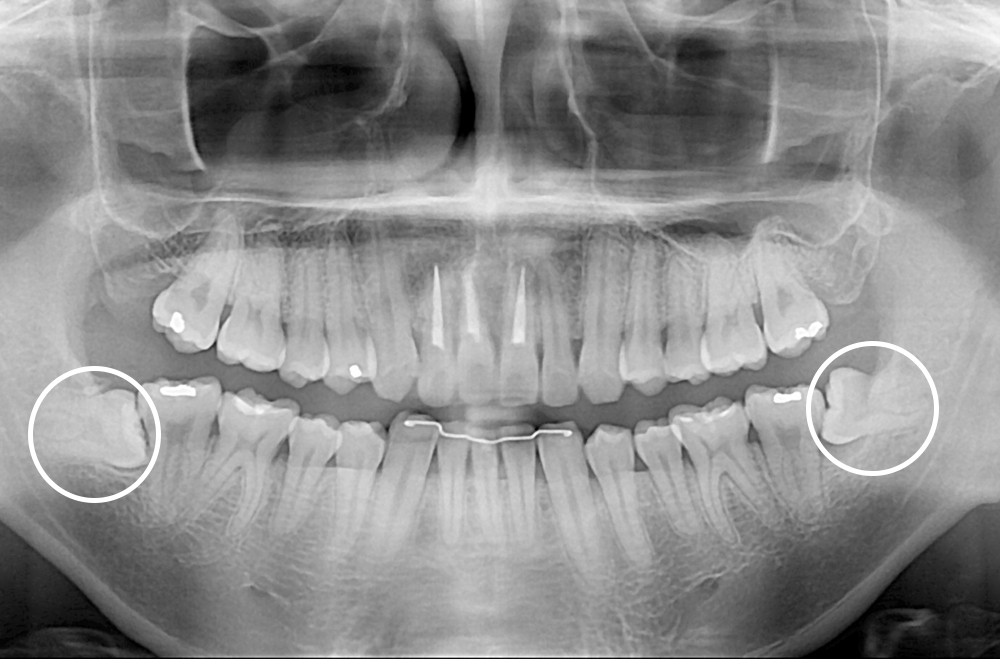

[사랑니] 매복 사랑니 발치

치료후 : 2019-01-24

세종치과는 구강악안면외과학 박사이신 원장님이 발치하는 치과입니다.